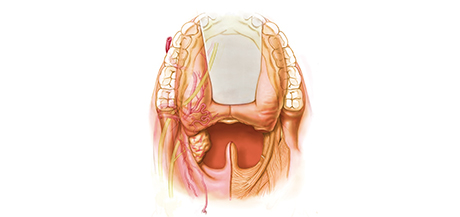

Transoral Surgery for Head and Neck Cancer is designed to give Otolaryngologists, Head and Neck Surgeons, Oral Maxillofacial Surgeons, and Head and Neck Oncologists a focused educational experience in transoral endoscopic techniques for resecting primary head and neck tumors. Both transoral laser and robotic surgery will be featured, as well as flexible laser surgery in inpatient and outpatient environments.

An optional cadaveric hands-on workshop will provide participants with opportunities to perform various transoral procedures with laser technologies and delivery systems. Renowned faculty will emphasize fundamental transoral anatomy, microsurgical and robotic techniques, and wound exposure, as well as other transoral techniques. Workshop participants will gain experience in the art of tumor exposure using various retractors and appropriate and safe use of multiple transoral systems.

• Identify key features of “inside-out” anatomy of the upper aerodigestive tract.